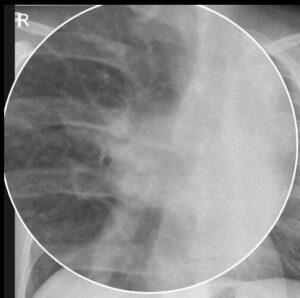

Eine sorgfältige Analyse des Lungenhilus ist essenziell, da viele pulmonale und kardiale Erkrankungen in diesem Bereich radiologisch erkennbar werden. Hier bündeln sich Bronchien, Gefäße und Lymphknoten. Überlagerungen sind häufig. Eine strukturierte Analyse erhöht die Befundsicherheit. Sie reduziert das Risiko, relevante Zeichen zu übersehen. Dieser Beitrag bietet einen kompakten Leitfaden für die tägliche Praxis.

Der rechte Hilus liegt in der Regel etwas tiefer als der linke. Zentrale Pulmonalarterien erscheinen prominenter und verjüngen sich zur Peripherie. Konturen sind glatt und gleichmäßig. Lymphknoten sind im Normalfall nicht abgrenzbar. Diese Normregeln sind der Vergleichsmaßstab für Pathologie.

Hinweise auf pulmonaIe Hypertonie sind vergrößerte zentrale Pulmonalarterien und periphere Gefäßverarmung. Manchmal wölbt sich der Truncus pulmonalis. Ursachen reichen von Linksherzerkrankungen bis zur chronischen Thromboembolie.

Vergrößerte Lymphknoten wirken rundlich oder gelappt. Konturen sind schärfer als bei Gefäßen. Häufige Ursachen sind Sarkoidose, Tuberkulose, Lymphom und Metastasen. Symmetrie hilft: die Sarkoidose zeigt oft beidseitige, symmetrische Hilusadenopathien. Die CT klärt Verteilung, Dichte und Verkalkungen.

Eine Hilusmasse kann von einem bronchogenen Karzinom oder Lymphom ausgehen. Achten Sie auf asymmetrische Hilushöhen, unruhige Konturen und Mediastinalverlagerung. Ein begleitender Atelektasekeil spricht für eine zentrale Bronchusobstruktion.